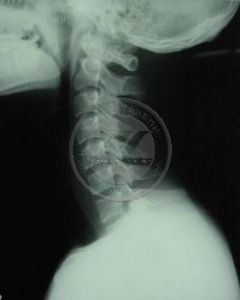

1、X線檢查

齒狀突發育畸形--X線檢查2、CT掃描檢查